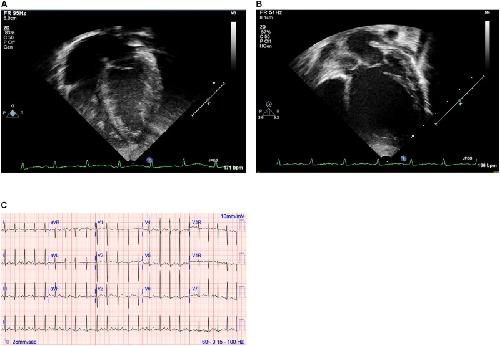

Quantitative Phenotyping of Xenopus Embryonic Heart Pathophysiology Using Hemoglobin Contrast Subtraction Angiography to Screen Human Cardiomyopathies., Deniz E, Jonas S, Khokha MK, Choma MA., Front Physiol. January 1, 2019; 10 1197. |

Familial Dilated Cardiomyopathy Associated With a Novel Combination of Compound Heterozygous TNNC1 Variants., Landim-Vieira M, Johnston JR, Ji W, Mis EK, Tijerino J, Spencer-Manzon M, Jeffries L, Hall EK, Panisello-Manterola D, Khokha MK, Deniz E, Chase PB, Lakhani SA, Pinto JR., Front Physiol. January 1, 2019; 10 1612. |

Analysis of Craniocardiac Malformations in Xenopus using Optical Coherence Tomography., Deniz E, Jonas S, Hooper M, N Griffin J, Choma MA, Khokha MK., Sci Rep. February 14, 2017; 7 42506. |